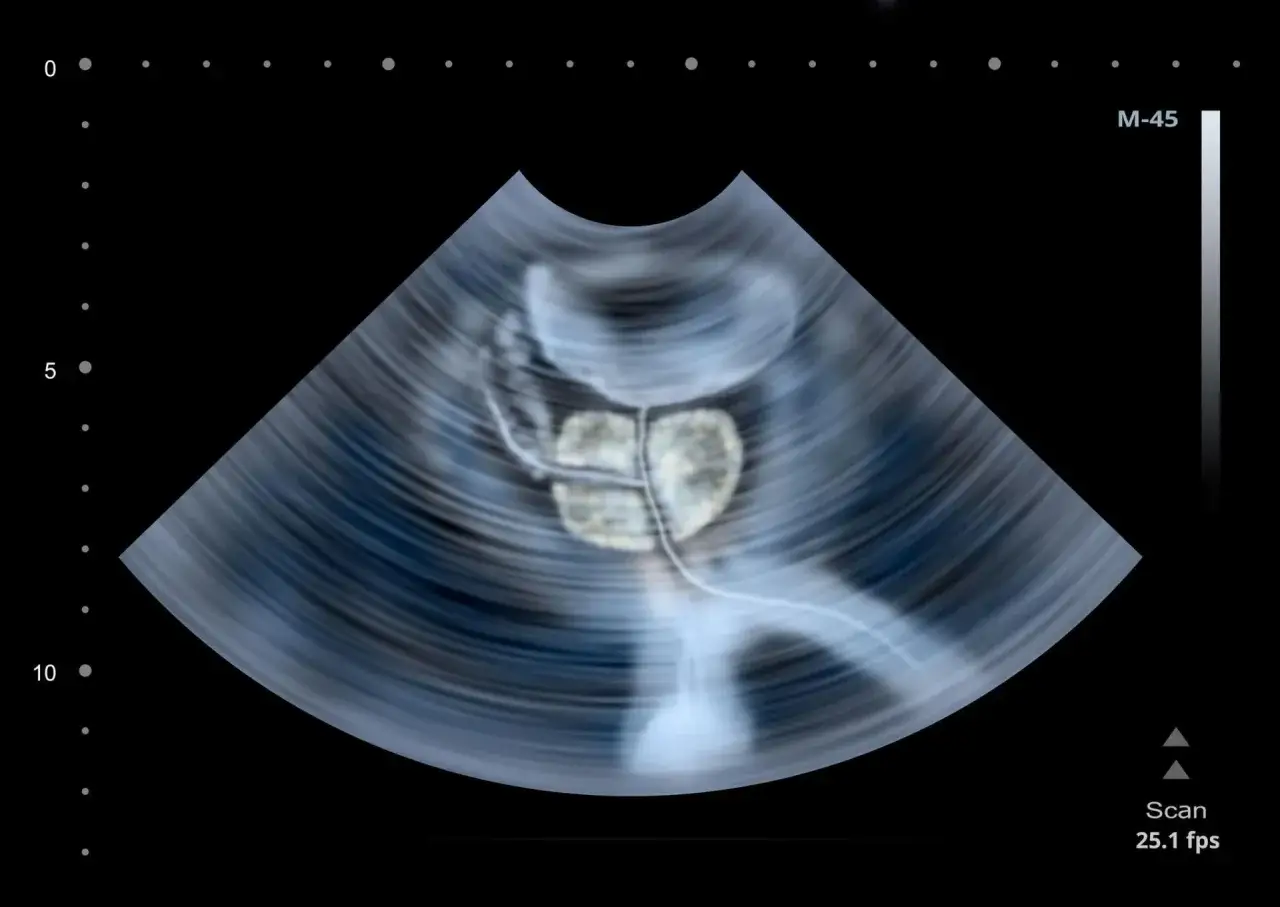

- USG prostaty: To badanie obrazowe, które pozwala ocenić wielkość, kształt i strukturę prostaty. Może być wykonywane przez powłoki brzuszne (wymaga wypełnienia pęcherza) lub, co jest znacznie dokładniejsze, transrektalnie (TRUS), czyli przez odbyt. USG transrektalne jest kluczowe przy planowaniu ewentualnej biopsji.

- Rezonans magnetyczny (mpMRI): To nowoczesne i bardzo precyzyjne badanie obrazowe. Rezonans multiparametryczny (mpMRI) jest obecnie często wykorzystywany do lokalizacji podejrzanych ognisk w prostacie jeszcze przed wykonaniem biopsji, co zwiększa jej celność.